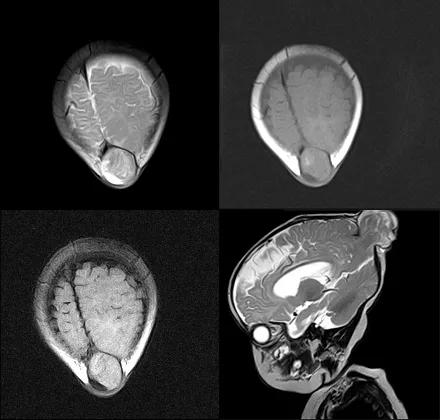

先天性脑膜膨出

先天性脑膜脑膨出(Congenital meningoencephalocele):脑膜或脑膜膨脑膨出是指脑膜或脑膜和脑组织从颅骨的先天性缺损即颅裂向外膨出

颅裂的发生与神经管的闭合不全以及中胚层的发育停滞有关,颅内容物多从枕囟、眉间囟或其他部位突出于颅外,其内容物包含硬膜、蛛网膜及脑实质

MR 主要表现为与颅内连续的脑组织从颅骨缺损处向外膨出

case 1:男性,6 月,后顶枕部包块进行性增大 4 月余。

诊断:脑膜脑膨出。